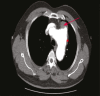

Elderly Man with Acute Chest Pain